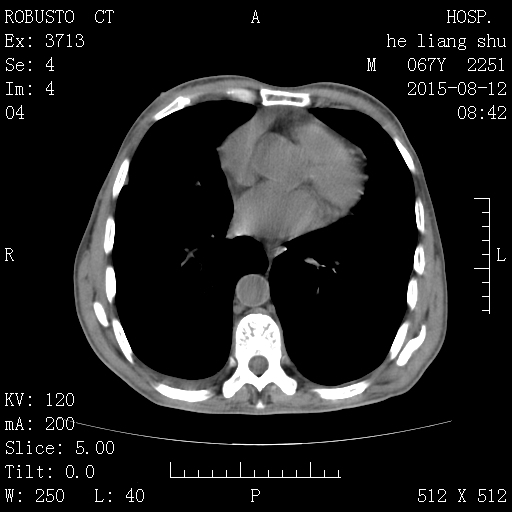

肝内可见多个结节,肝外形欠规则,脾大,肝脾周、肠管间、右侧胸腔、心包均可见液体密度影,心腔密度低于室间隔,考虑结节性肝硬化,不除外肝癌可能,大量腹水,贫血。

1、结节性肝硬化,转化为肝癌不除外;

2、腹腔大量积液;

3、脾脏代偿性增大;

4、胸腔积液;

5、心包积液;心腔密度减低,低于室间隔密度,提示贫血;

6、食管下段前壁似增厚,请结合食管镜除外占位可能。

1、肝硬化、腹水、门脉高压伴再生结节形成。

2、贫血。

肝内多发硬化结节、腹水、门脉高压,不排外转化肝癌......也不能增强了吧,腹穿解决问题。